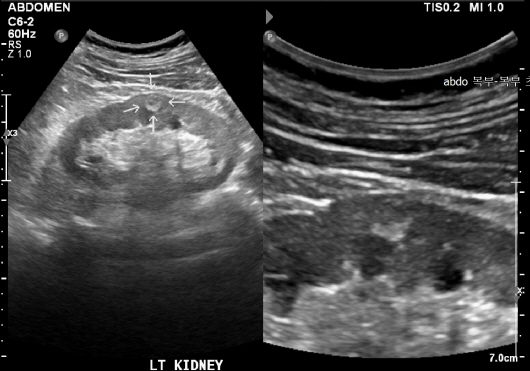

신장 질환

신장은 인체의 대사 노폐물을 제거하고 수분 및 전해질 균형을 유지하는 중요한 역할을 합니다. 신장에 문제가 발생하면 체내의 여러 기능이 부정적인 영향을 받을 수 있습니다. 복부 CT는 신장 결석, 신장 종양 및 기타 신장 관련 질환을 진단하는 데 도움을 줍니다.

신장 결석: 예방법과 치료 방법

신장 결석은 신장에서 형성된 경결된 물질로, 통증을 유발할 수 있습니다. 복부 CT는 결석의 위치와 크기를 정확하게 파악할 수 있으며, 이 정보를 바탕으로 적절한 치료 방법을 결정하는 데 매우 중요합니다. 결석이 발견되면, 물리치료, 약물 치료, 혹은 필요 시 수술이 고려될 수 있습니다. 신장 결석은 수분 보충과 균형 잡힌 식사를 통해 예방할 수 있으므로, 생활 방식의 변화 또한 동반되어야 합니다.